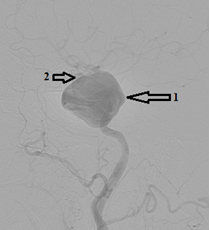

- Краткая информация о пациенте: Пациентка, 72 года. С 2016 года наблюдается по поводу аневризм левой ВСА. 15.09.2016 г. в ФГАУ «НИИ нейрохирургии им. акад. Н.Н. Бурденко» выполнена селективная церебральная ангиография. От оперативного вмешательства решено было воздержаться ввиду неблагоприятной анатомии несущего аневризму сосуда. В августе 2018 года выполнено МСКТ сосудов головного мозга, на которой выявлено увеличение размеров аневризмы кавернозного и супраклиноидного сегментов в сравнении с предыдущими данными от 30.03.2016 г. Была проконсультирована нейрохирургом клиники нейрохирургии ВМедА повторно. Было решено осуществить попытку эндоваскулярного лечения аневризм левой внутренней сонной артерии. Во время предоперационной подготовки при выполнении МСКТ-ангиографии брахиоцефальных сосудов была оценена анатомия ветвей дуги аорты и прослежен их ход в шейном отделе. Учитывая подтвержденные данные о неблагоприятной анатомии для трансфеморального доступа, было принято решение об изменении тактики хирургического лечения. Решено выполнить гибридное оперативное вмешательство: выделение левой общей сонной артерии, редрессацию патологических деформаций и эндоваскулярную имплантацию устройства, отклоняющего поток (FRED), на уровне аневризм левой внутренней сонной артерии. С учётом результатов генетического исследования на определение эффективности терапии препаратом Клопидогрел пациентке за неделю до госпитализации назначена двойная антиагрегантная терапия препаратом Плавикс 75 мг 1 раз в день и ТромбоАСС 100 мг 1 раз в день. Эффективность терапии оценена непосредственно перед началом оперативного вмешательства при помощи системы VerifyNow® — уровень подавления агрегационной функции тромбоцитов составил 36 %.

2 этап. По методике Сельдингера в левую ОСА установлен радиальный интродьюсер 6F. При помощи гидрофильного проводника Radifocus интракраниально введен направляющий катетер Fargo 6F. Затем при помощи микропроводника Traxcess14 область поражения – фузиформная аневризма кавернозного сегмента преодолена. Проводник заведен в левую СМА до уровня М3. Потом осуществлена замена микрокатетера на манипуляционный катетер Headway 27, кончик которого позиционирован в М1-сегменте левой СМА. Далее введено устройство, отклоняющее поток (FRED 4*32*26 мм). Стент позиционирован и имплантирован из-под бифуркации ВСА с перекрытием области поражения (3-х аневризм ВСА). Стент раскрыт полностью. При контрольной ангиографии левая ВСА проходима, стент прилежит к стенкам артерии; отмечается длительная стагнация контрастного вещества в гигантской аневризме; церебральные ветви проходимы, бессосудистых зон нет.